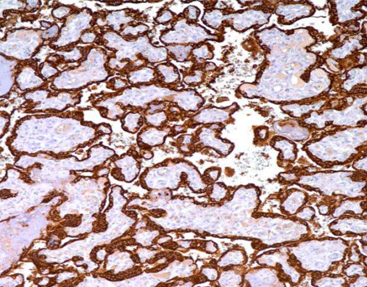

[As Figure shows]

Choriocarcinoma tissue stained with HPL